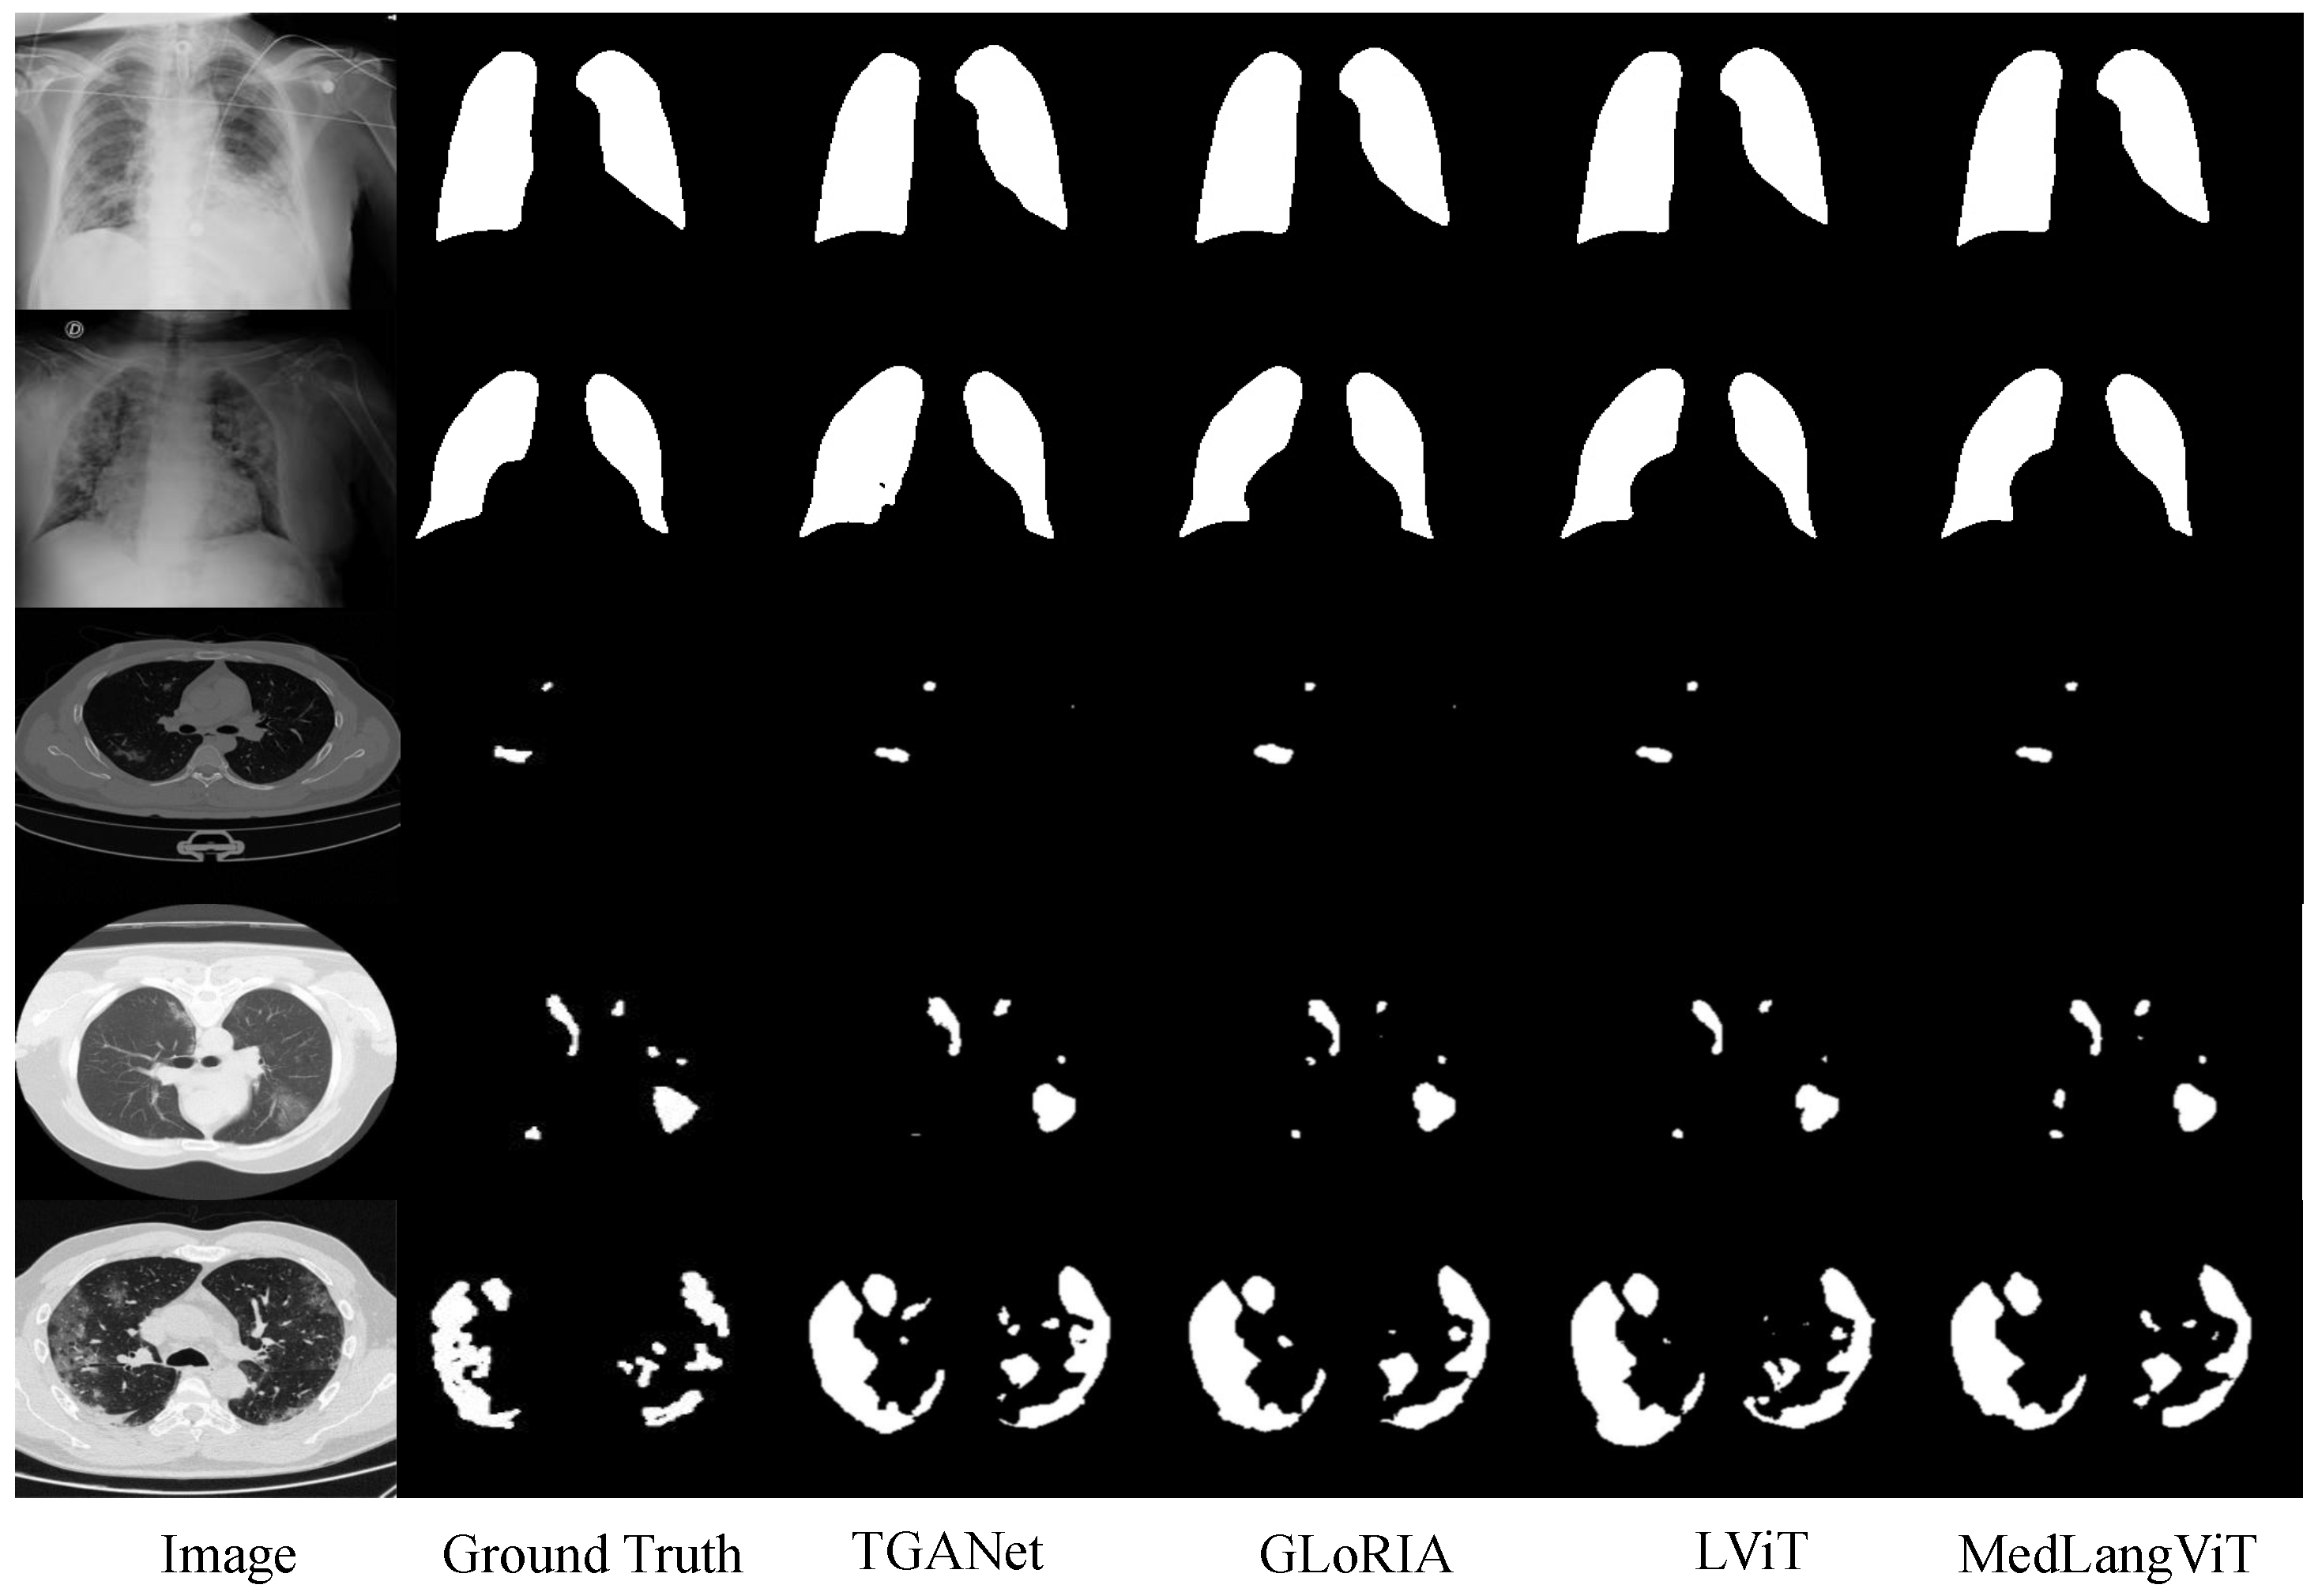

Since the quantitative results of image-only models are consistently lower than those of text–image models, we performed qualitative analysis only on the text–image models. The qualitative results of MedLangViT and other state-of-the-art methods on the MosMedData+ and QaTa-COV19 datasets are shown in Figure 6. To demonstrate segmentation performance across varying lesion sizes, we present representative results from the MosMedData+ dataset categorized into three groups: small, medium, and large lesions. As shown in Figure 6, while segmentation accuracy for small and medium lesions shows comparable performance across methods, our approach achieves significantly superior shape fidelity and topological continuity for large lesions, more closely aligning with the ground truth annotations. The qualitative results demonstrate that MedLangViT exhibits robust semantic segmentation capabilities compared with other state-of-the-art multimodal segmentation methods. Due to the advantage of integrating both text and image information into a single encoder, MedLangViT achieves finer segmentation boundaries.

Figure 6.

The qualitative results of different methods on QaTa-COV19 and MosMedData+ datasets.